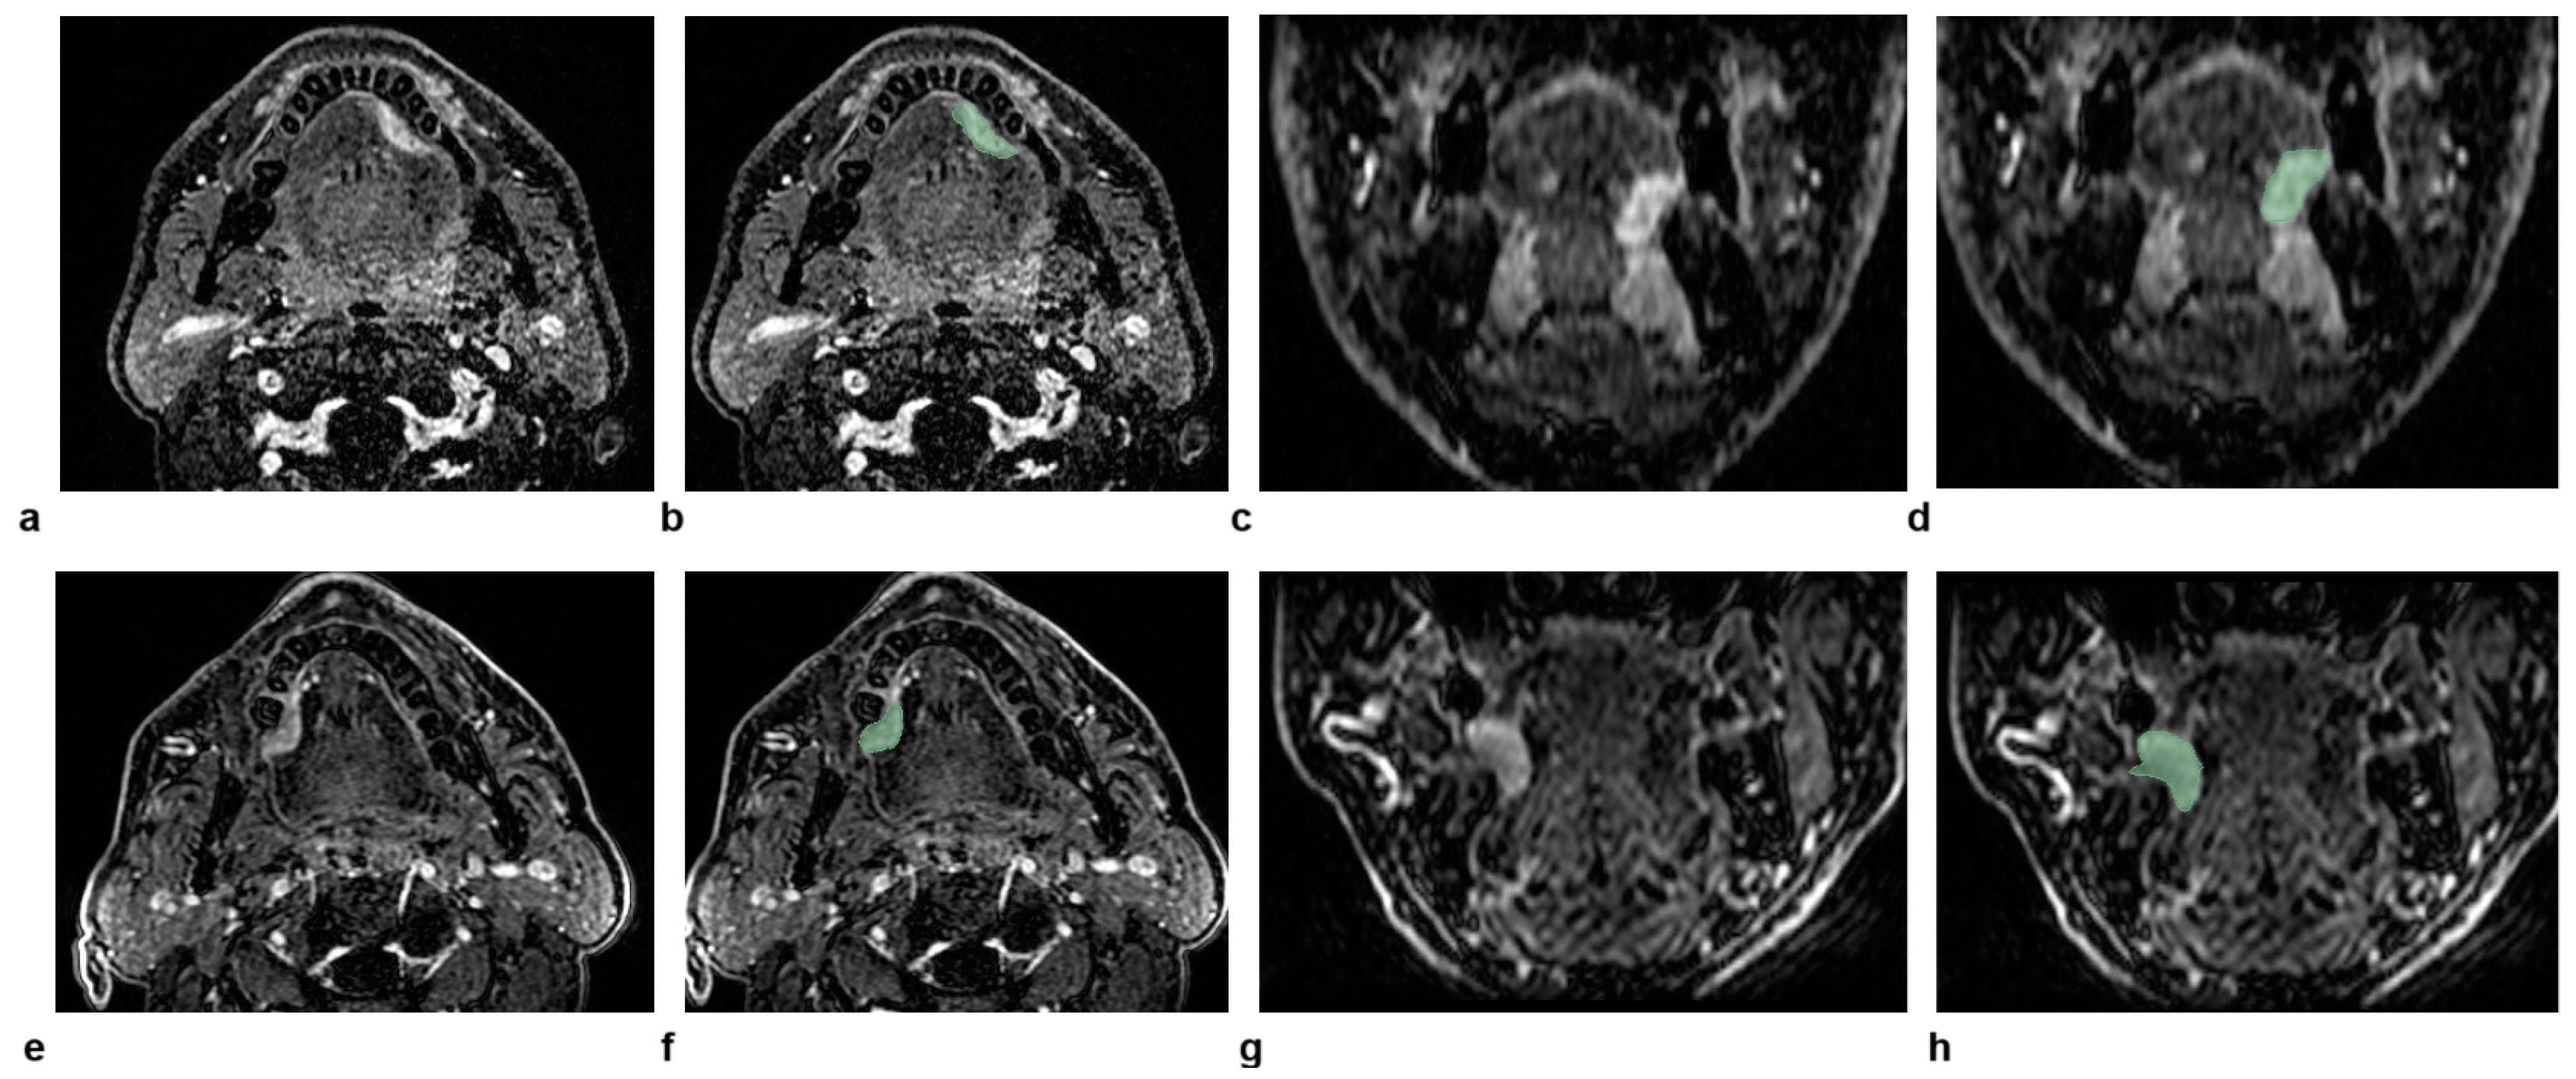

3.2. Illustrative Cases

Two representative patients with the same radiological staging (cT2N0) but different clinical outcomes are illustrated in Figure 4. The radiomic-only model and all of the combined models provided the correct predictions for both patients. This can be explained considering that the values of large-area high-gray-level emphasis, large-dependence high-gray-level emphasis, and long-run emphasis were all lower in the patient without recurrence compared to the patient with recurrence (6.6 × 104, 4.7 × 103, and 1.1 versus 1.0 × 105, 1.5 × 104, and 1.2, respectively).

Figure 4. The figure shows dynamic high-spatial-resolution T1-weighted images after contrast medium administration in the axial and coronal planes of two patients with the same radiological staging (cT2N0) but different clinical outcomes, for whom the radiomic-only model and all combined models provided the correct predictions. In the top row (ad), the images represent a 58-year-old male patient who did not experience a recurrence, with the corresponding delineated lesion outlined in green on the same planes (b,d). In the bottom row (eh), the images represent a 71-year-old male patient with a recurrence. Similarly, the axial and coronal images (e,g) show the lesion after contrast medium administration, with the delineated lesion outlined in green (f,h).